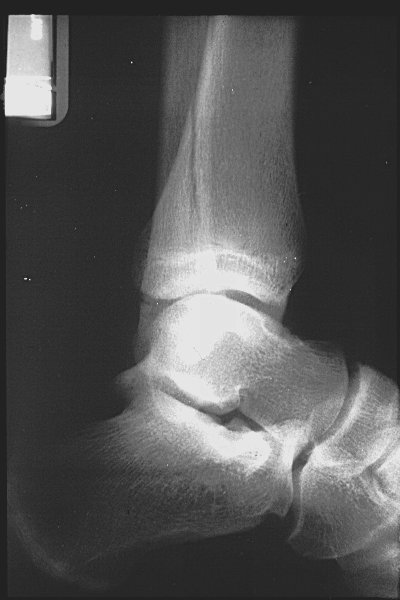

Return to Triplane Fracture